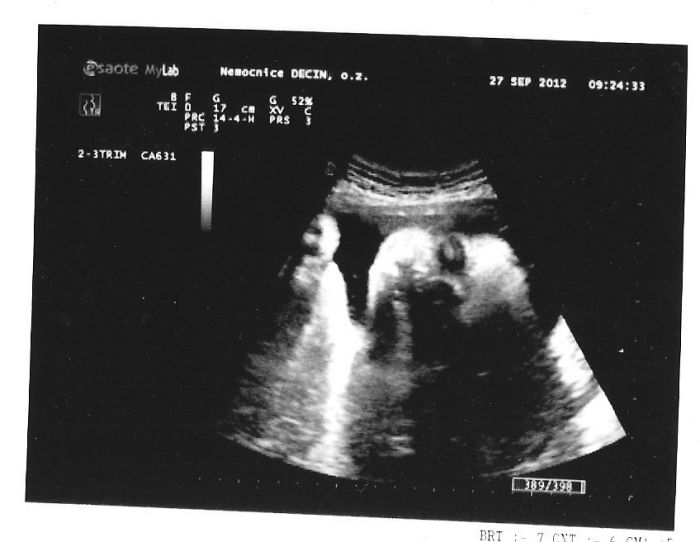

Já byla na trochu mimořádné kontrole včera - malá byla hlavičkou nahoru - dneska jsem byla znova - kvůli tlaku, doktor mi udělal znovu UZ, aby zkontroloval srdíčko - a malá už zas byla hlavičkou dolů... takže mimi se fakt v tuhle dobu ještě může točit jak chce ;-) Ale určitě odpočívej, už si toho odpočinku zas tolik neužijeme :-)

Jinak když už mi dneska dělal doktor UZ, tak jsem ho poprosila, ať mi koukne ještě na tu placentu - na to jsem včera zapomněla - a udělal mi radost - placenta už je vytažená minimálně 3 cm od branky, takže to nebude snad muset být císař... a to mi na to vytažení dával 1-2 %... :-)

Tak máme za sebou poslední ultrazvuk, jsme ukázkové miminko (podle paní doktorky), máme bez pěti gramů 2kila, 40centimetrů, jsme hlavičkou dolů, zdravý a krásňoučký :-) Miminko na nás mrkalo a mávalo jako panenka, jestli to bude chlapeček, bude to naprosto krásná holčička :-D